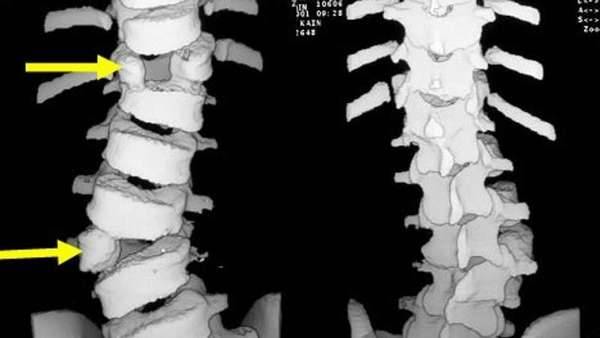

На снимке можно увидеть явные признаки полного или неполного сращения поясничного позвонка L5 с крестцом и крыльями подвздошной кости.

Форма и степень ассимиляции переходного позвонка весьма разнообразны (рис. 1 и 2). Ассимиляция проявляется главным образом в изменении поперечных отростков позвонка. В одних случаях наблюдается только расширение одного или обоих поперечных отростков в последнем поясничном позвонке, в других — выраженные их деформации, характеризующиеся соединением с боковыми массами крестца.

Соединения бывают костные, посредством хряща, соединительной ткани и иногда в виде сустава, что и образует неподвижные и подвижные формы ассимиляций. Первые являются бессимптомными аномалиями, вторые могут осложняться деформирующим артрозом и сопровождаться теми или иными клиническими проявлениями (боли, ограничение подвижности, иногда рецидивирующие радикулиты и люмбоишиальгия).

Среди полных форм переходного позвонка различают костные, суставные и костно-суставные формы. При костных формах поперечные отростки позвонка полностью спаиваются с боковыми массами крестца, при суставных — образуются синхондроз, синартроз и истинный сустав; костно-суставные формы характеризуются синостозом одного из увеличенных поперечных отростков и синхондрозом другого поперечного отростка с боковой массой крестца.

Суставные отростки ассимилированного поясничного позвонка обычно остаются обособленными, не сращенными даже при полном костном слиянии поясничного позвонка с крестцом, что указывает на происхождение I крестцового позвонка при шестипозвонковом крестце из поясничного позвонка. Неполные ассимиляции также бывают двусторонними и односторонними.